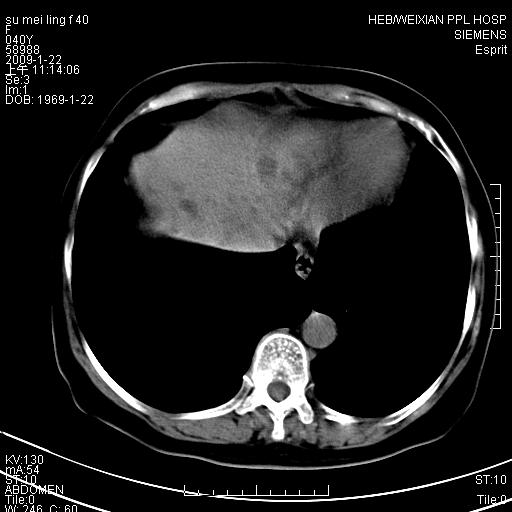

主因食欲不振检查。b超检查肝内片状低密度影。

图象的序列乱,病史也简单,单看这几幅图片考虑——肝囊肿?转移瘤?建议强化

以肝多发性囊肿可能大

我个人认为转移瘤可能性大!建议增强!

考虑多发肝小囊肿,建议增强,不排除囊性转移可能。

多发肝囊肿或caroli

肝内多发囊性低密度灶,以肝囊肿可能性大;建议必要时行进一步检查。

囊性病变沿胆管走向,首先考虑肝内胆管囊肿(caroli)、多发肝囊肿不除外